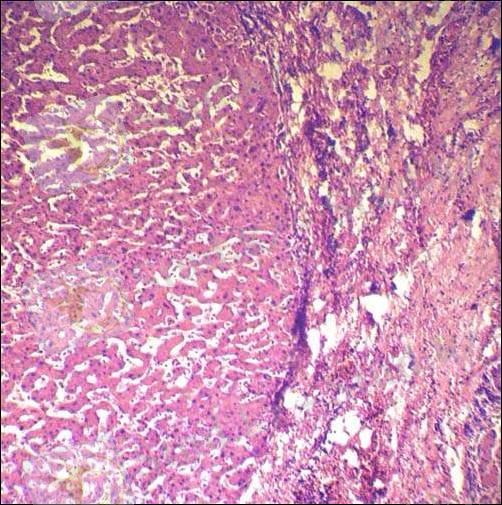

Вильсон - Коновалов ауруы кезіндегі бауырдың өзгерісі

(Цироз) .

Науқас бауырының биопсиясы.

Бауырдың пункциялық биопсиясы:гистологиялық, гистохимиялық зерттеледі. Қалыпты жағдайдағы бауырдағы мыстың концентрациясы: құрғақ массасы 50 млг∕ кг-дан төмен, ылғал массасы 10 млг∕кг-дан төмен.